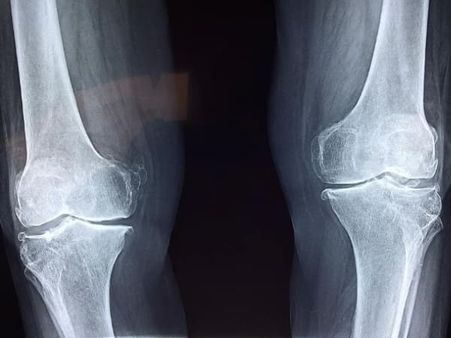

The trailer of the much-anticipated film Dil Bechara, starring late actor Sushant Singh Rajput and debutante Sanjana Sanghi was released on Monday (6 July). The film plot revolves around the journey of two lead characters, Kizie (Sanjana Sanghi), a cancer patient and Manny (Sushant Singh Rajput), a survivor of osteosarcoma, and how he teaches her to live life to the fullest. As soon as the film trailer was out, it got praises from fans and celebrities. Here's what you should know about osteosarcoma, the disease Sushant Singh Rajput has in this film.

Osteosarcoma (OS) also called osteogenic sarcoma is the most common type of bone cancer that affects 3.4 per million people worldwide every year. It is the third most common cancer in adolescents. Children under the age of 15 are also diagnosed with osteosarcoma and it is rare among children who are below five years of age. However, osteosarcoma can develop at any age [1].

Osteosarcoma develops in the cells that form bones. It most often affects the long bones like the ones found in the arms and legs. Osteosarcoma mainly occurs near the ends of the long bones, such as the femur (thigh bone) near the knee, proximal tibia (shin bone) near the knee and proximal humerus (upper arm bone) near the shoulder.

However, osteosarcoma can also occur in other parts of the body such as in the pelvis (hips), jaw and shoulder bones which is common in older adults [2], [3].

Diagnosis Of Osteosarcoma

The doctor will perform a thorough physical examination and ask about the symptoms and medical history. After which, the doctor will conduct certain tests to diagnose osteosarcoma. These diagnostic tests include X-ray, MRI, CT scan, PET scan, bone scan and biopsy [10].